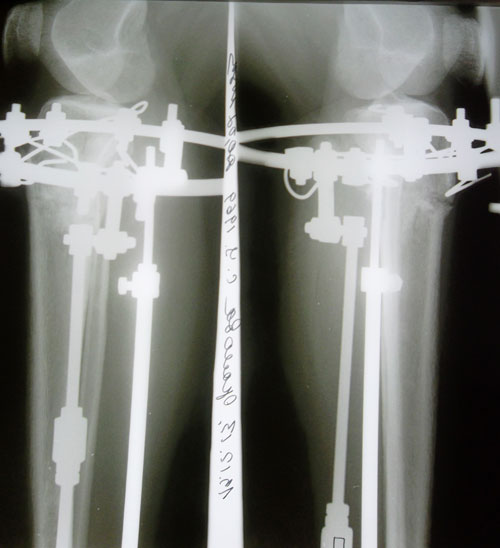

рентген в 76 дней.

Сращение отличное, предполагаемая дата снятия аппаратов - 06 января 2014г.